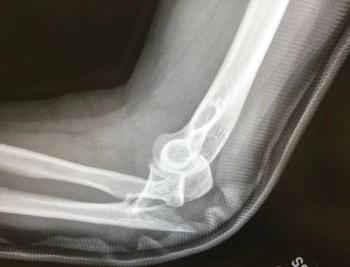

A 20-something young man is in the ED after a fall off a scooter while doing tricks. What do you see on the x-ray? What type of injury is it?